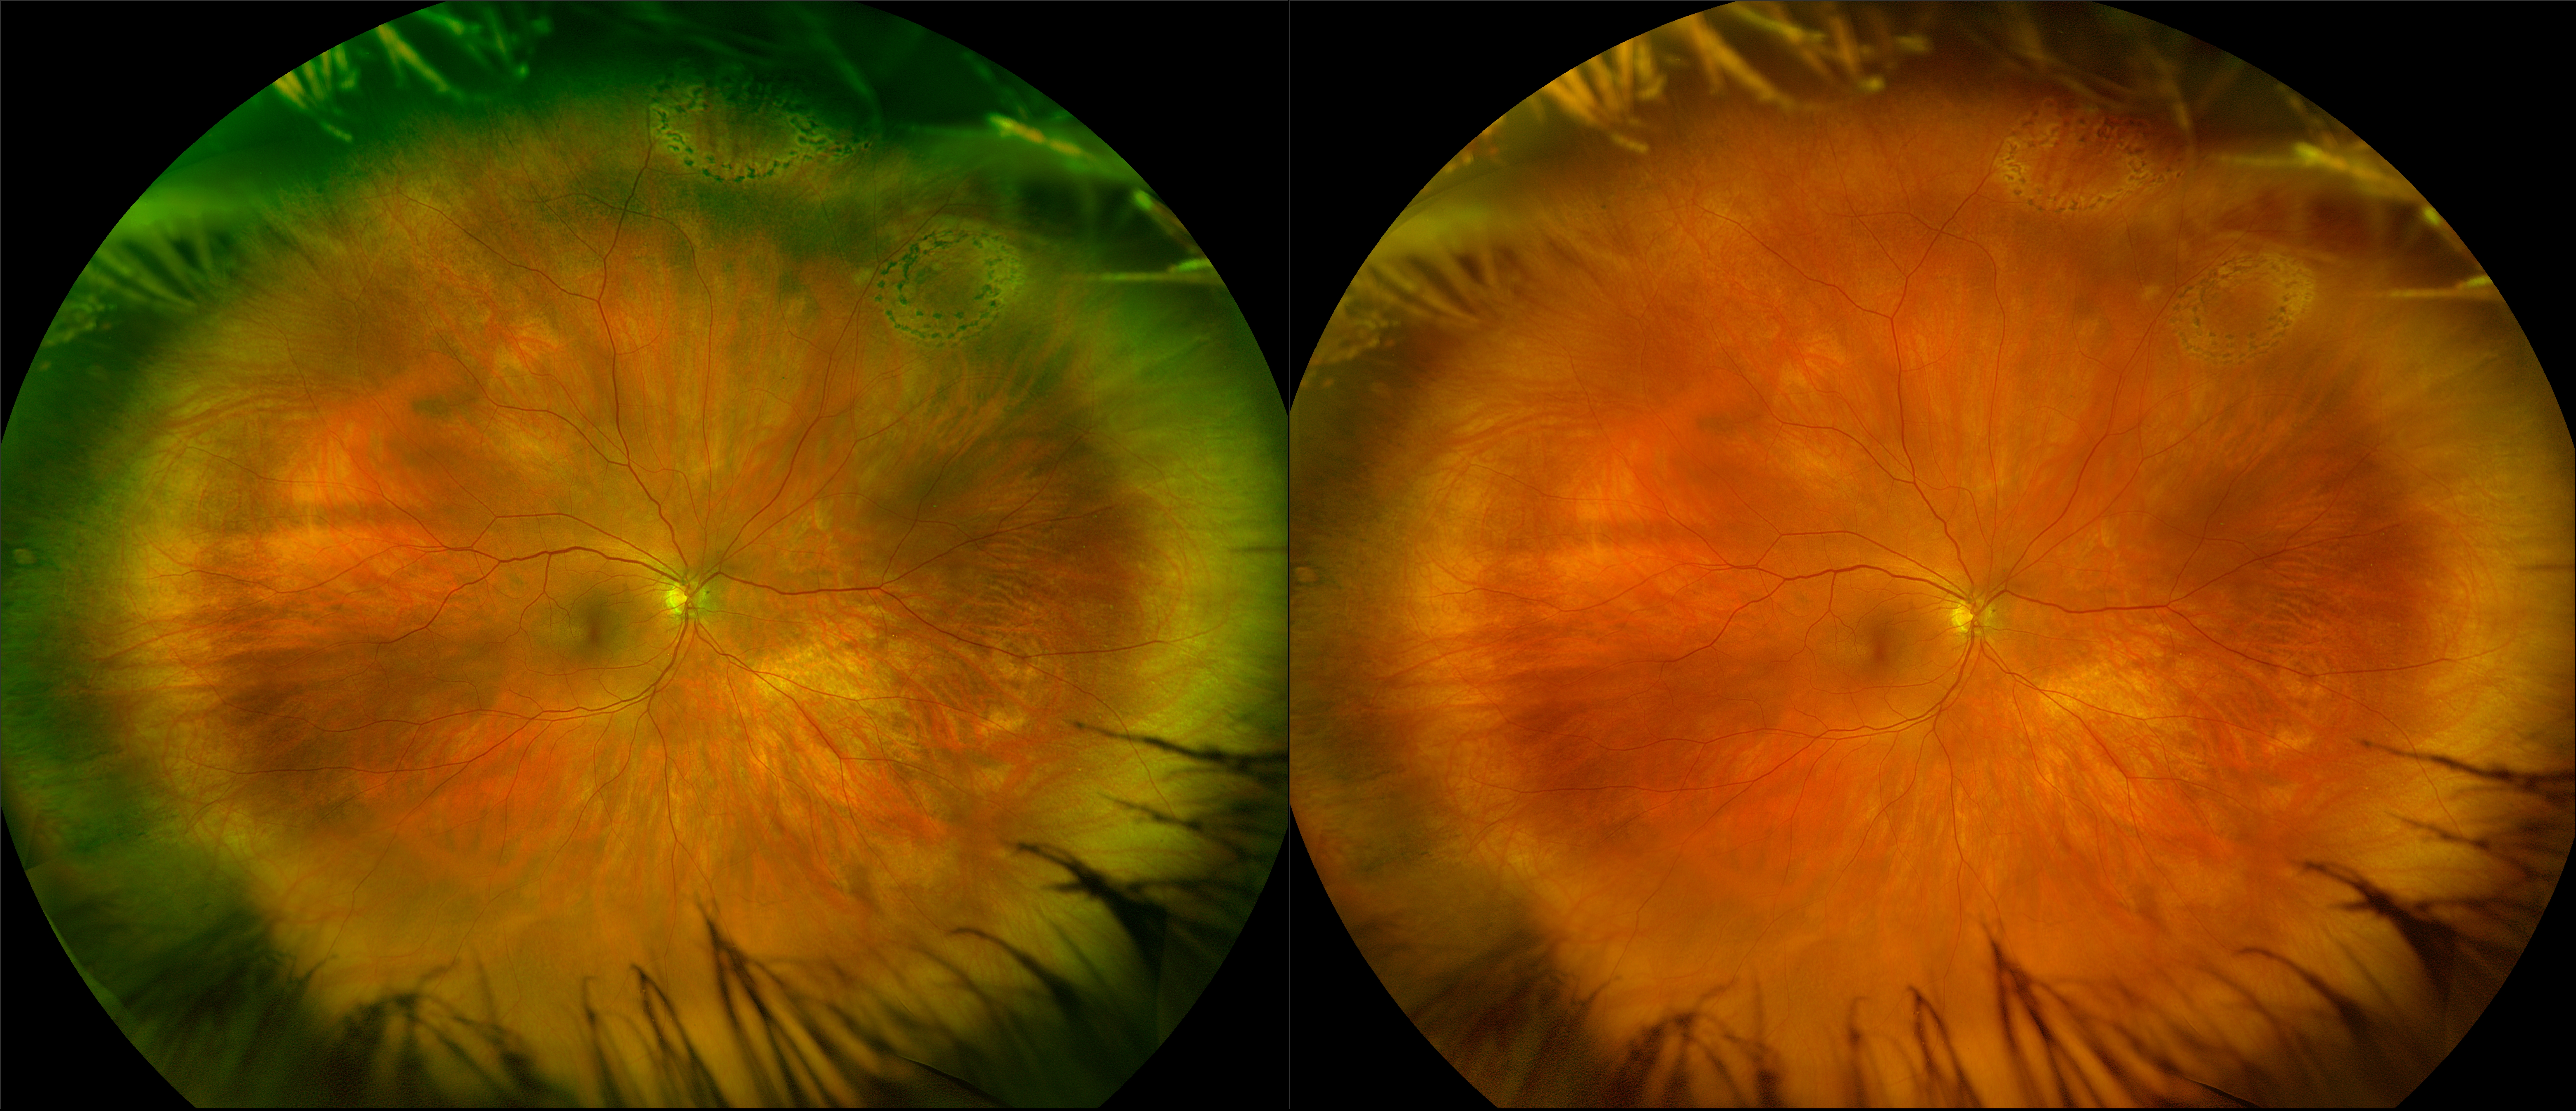

Monaco - Pigment Epithelial Detachment, RG, OCT

In some eyes, there may be small areas of the retina that are torn, or holes may develop. These areas, called retinal breaks, can lead to retinal detachment. Retinal breaks are often caused by traction from the vitreous, the gel that fills the back of the eye. Traction can occur as the vitreous pulls away from the retina, which occurs with age, trauma, surgery, inflammation, and near-sightedness.